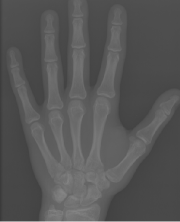

Refer to caption

Figure 1: (a) Original image. (b) Hand keypoint annotation used in BoNet [2]. (c) We convert the keypoints to bounding boxes which are used in our method to learn hand structure and extract local information.

The original annotations of hand pose are a series of points, and we need to use boxes for local extraction. Hence, during the training time, we replace the point annotations by boxes centered at the points (Fig. 1). We use the same loss function as in [13] to train RPN, and we denote the loss function of RPN as LRPNsubscript𝐿𝑅𝑃𝑁L_{RPN}.